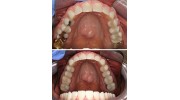

Photos